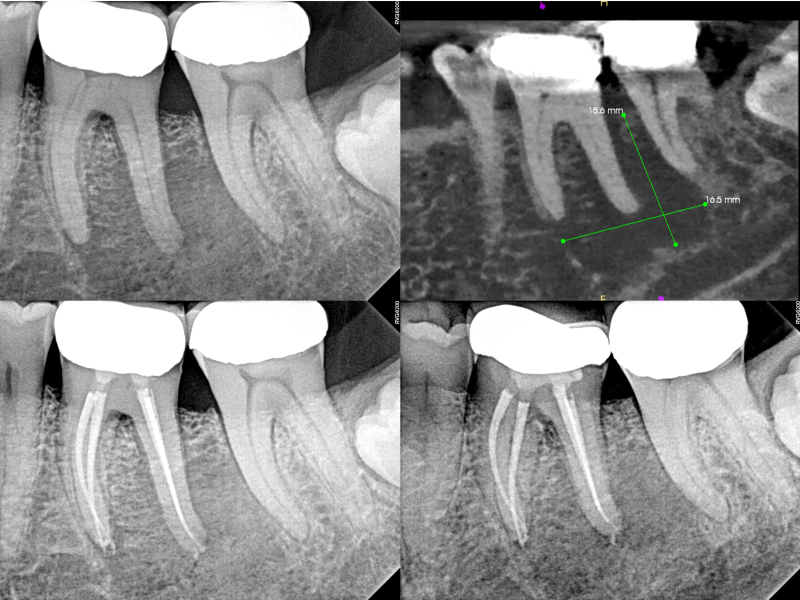

#18 Pulpal Necrosis and Normal Periapex

GentleWave

®

G4 with ProControl

™

Karen S. Potter, DDS

View Case Details